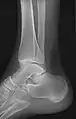

• Knee - AP and Lateral. Intra Condular projections on request

• Tibia and Fibula - AP and Lateral

• Ankle - AP/Mortice and Lateral

• Calcaneum - Axial and Lateral

Certain suspected conditions require specific projections. For example, skeletal signs of rickets are seen predominantly at sites of rapid growth, including the proximal humerus, distal radius, distal femur and both the proximal and the distal tibia. Therefore, a skeletal survey for rickets can be accomplished with anteroposterior radiographs of the knees, wrists, and ankles.[20]